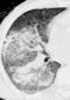

Chronic pulmonary hemorrhage